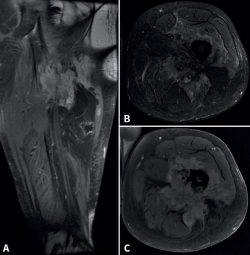

Cincuenta días tras el accidente se realizó fusión lumbar instrumentada L4-L5 con inserción de dispositivo intersomático por vía transforaminal derecha. En el segundo día postoperatorio presentó empeoramiento del dolor, objetivándose en la tomografía computarizada (Figura 2) malposición del tornillo L5 izquierdo que invadía el canal. Se reintervino a los 5 días corrigiendo el trayecto del tornillo. Sin embargo, persistió el dolor. La revaluación del caso, sumada a los hallazgos de EMG, motivó estudios complementarios de pierna y trayecto ciático (Figuras 3 y 4), detectándose una masa tumoral en el fémur izquierdo compatible con sarcoma fusocelular.

Figura 4. Resonancia magnética del fémur izquierdo. A: corte coronal en secuencia STIR, con masa de partes blandas de gran tamaño con afectación diafisaria femoral; B: corte axial en secuencia T2, con masa heterogénea con áreas de necrosis central; C: corte axial en secuencia T1 con supresión grasa, con compromiso del trayecto del nervio ciático por la masa tumoral.